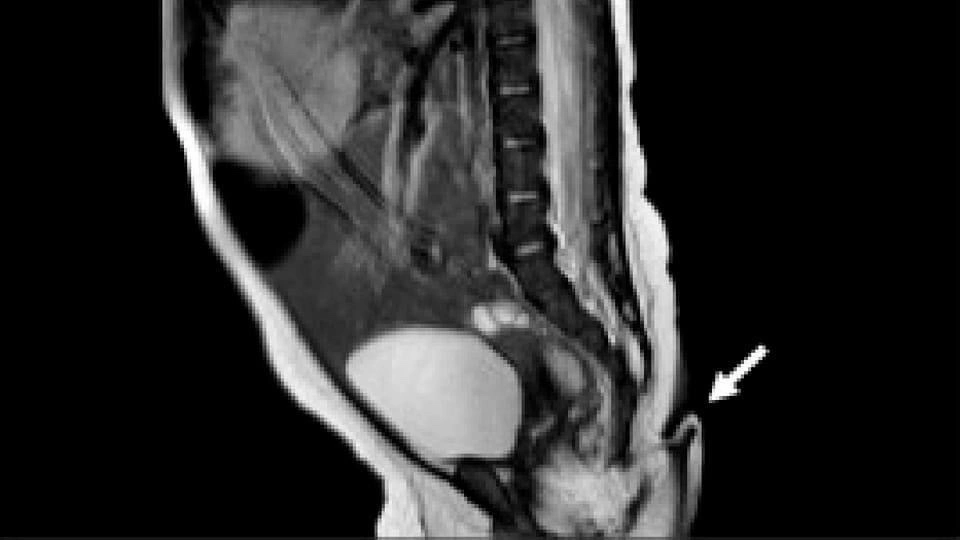

Asimismo, la resonancia magnética practicada no reveló anormalidades cerebrales, además, fue negativa para disrafismo posterior, y presentó médula espinal y cono medular de características normales. Entre tanto, la exploración auditiva y cardíaca fue normal, es decir: una bebé sana, por lo que fue dada de alta para seguimiento ambulatorio.